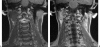

The anatomy of the jugular foramen is complex. It contains the lower cranial nerves and major vascular structures. Tumors that develop within it, or extend into it, provide significant diagnostic and surgical challenges. In this article, we describe the anatomy of the jugular foramen and outline an imaging protocol that can differentiate between lesions, thereby aiding diagnosis and facilitating management.